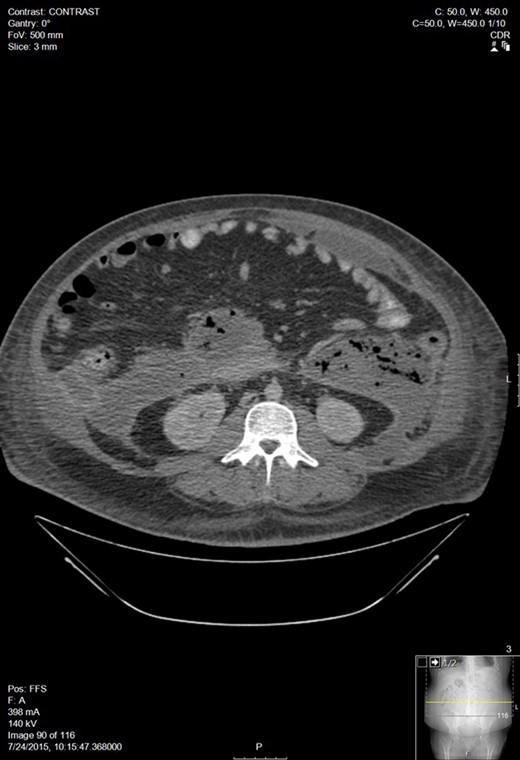

A 30-year-old man with a past medical history of hypertriglyceridemia presented to an outside ER with nausea, vomiting and abdominal pain. Lab studies were significant for pancreatitis (lipase 2730), hypertriglyceridemia (1594), blood glucose of 389 and BUN/Cr of 17/1.3. A CT of the abdomen showed AP. A subsequent lab draw showed BUN/Cr to 27/3.8, decrease in lipase to 565, increase in triglycerides to 4243, and a BNP 15. He was transferred to our facility following worsening hypoxemia. A CT scan was performed: representative sections shown below demonstrated walled off pancreatic necrosis (Fig. 1). He was in acute renal failure on presentation and started on continuous renal replacement therapy. The renal failure resolved, he completed a 7-day course of imipenem/cilistatin and was eventually discharged 11 days after admission.

Worsening walled off pancreatic necrosis with extension to the paracolic gutters.